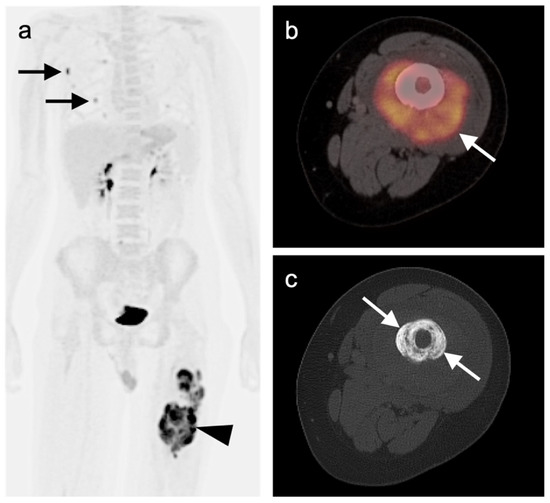

- Zidan, L.; Iravani, A.; Kong, G.; Akhurst, T.; Michael, M.; Hicks, R.J. Theranostic implications of molecular imaging phenotype of well-differentiated pulmonary carcinoid based on 68Ga-DOTATATE PET/CT and 18F-FDG PET/CT. Eur. J. Pediatr. 2020, 48, 204–216. [Google Scholar] [CrossRef]

- Venkitaraman, B.; Karunanithi, S.; Kumar, A.; Khilnani, G.C.; Kumar, R. Role of 68Ga-DOTATOC PET/CT in initial evaluation of patients with suspected bronchopulmonary carcinoid. Eur. J. Pediatr. 2014, 41, 856–864. [Google Scholar] [CrossRef]

- Komek, H.; Can, C.; Urakçi, Z.; Kepenek, F. Comparison of (18F)FDG PET/CT and (68Ga)DOTATATE PET/CT imaging methods in terms of detection of histological subtype and related SUVmax values in patients with pulmonary carcinoid tumors. Nucl. Med. Commun. 2019, 40, 517–524. [Google Scholar] [CrossRef]